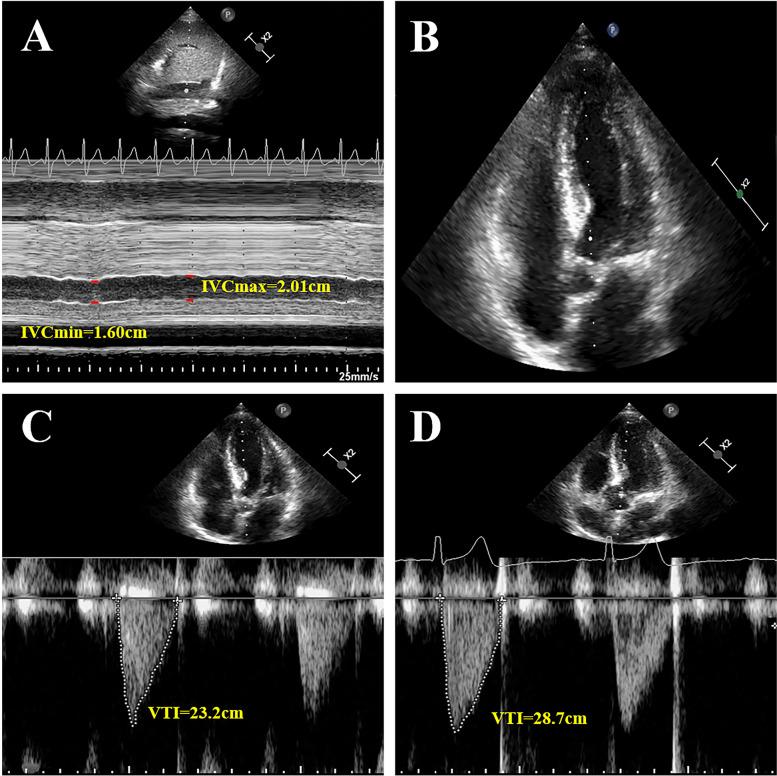

A total of fifty-six patients after abdominal surgeries in the anesthesia intensive care unit ward were included. All patients received ultrasonographic examination before and after the fluid challenge of 5 ml/kg crystalloid within 15 min. The same measurements were performed when the patients were extubated. The IVC diameter, blood flow velocity-time integral of the left ventricular outflow tract, and cardiac output (CO) were recorded. Responders were defined as an increment in CO of 15% or more from baseline.

There were 33 (58.9%) mechanically ventilated patients and 22 (39.3%) spontaneously breathing patients responding to fluid resuscitation, respectively. The area under the curve was 0.80 (95% CI: 0.68-0.90) for the IVC dimeter variation (cIVC1) in mechanically ventilated patients, 0.87 (95% CI: 0.75-0.94) for the collapsibility of IVC (cIVC2), and 0.85 (95% CI: 0.73-0.93) for the minimum IVC diameter (IVCmin) in spontaneously breathing patients. The optimal cutoff value was 15.32% for cIVC1, 30.25% for cIVC2, and 1.14 cm for IVCmin. Furthermore, the gray zone for cIVC2 was 30.72 to 38.32% and included 23.2% of spontaneously breathing patients, while 17.01 to 25.93% for cIVC1 comprising 44.6% of mechanically ventilated patients. Multivariable logistic regression analysis indicated that cIVC was an independent predictor of volume assessment for patients after surgery irrespective of breathing modes.